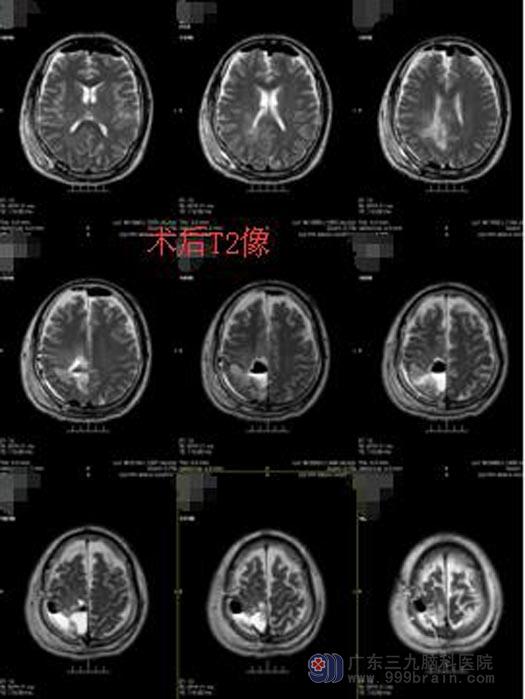

鲁明副院长主刀在唤醒麻醉下行右侧顶叶肿瘤切除术。手术中,利用导航准确地定位右侧顶叶的病变组织的位置,并在充分准备后唤醒患者完成医生要求的指定动作,利用电生理检测运动中枢,避开上下肢体运动中枢,显微镜下完整地切除肿瘤。手术过程顺利,患者肢体活动良好,待继续康复后出院。